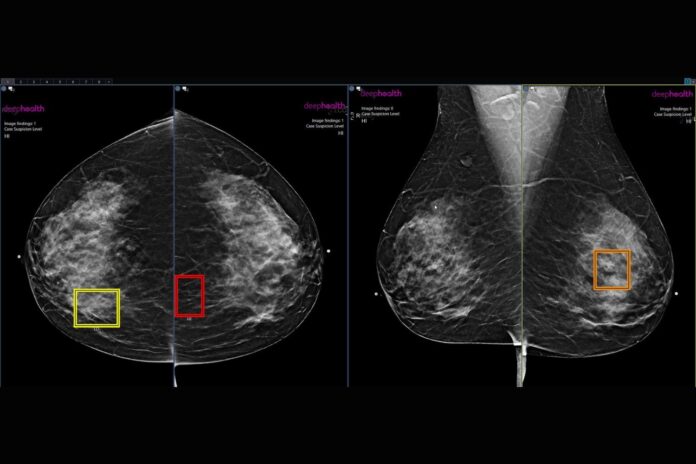

Researchers at this year’s annual meeting of the Radiological Society of North America (RSNA) have revealed that cancer was 21% more likely to be detected for women who paid extra for an AI-enhanced breast cancer screening program. Their findings, presented at the annual meeting and detailed in an RSNA statement, affirm AI’s potential to be a “second set of eyes” for radiologists.

The study considered 10 clinical practices offering patients a self-pay, FDA-compliant AI-powered screening mammography program. The X-rays of women who opted into the program were reviewed by a breast radiologist and then by the AI software. If the reviews were inconsistent with each other, a second radiologist would provide a third review.

“The AI-driven enhanced review program leverages AI in a novel workflow to ensure women with suspicious findings get expert level care that could help detect many more breast cancers early,” Haslam added. “The number of women electing for this program is now at 36% and growing, and the rate of cancer detection continues to be substantially higher for those women.”